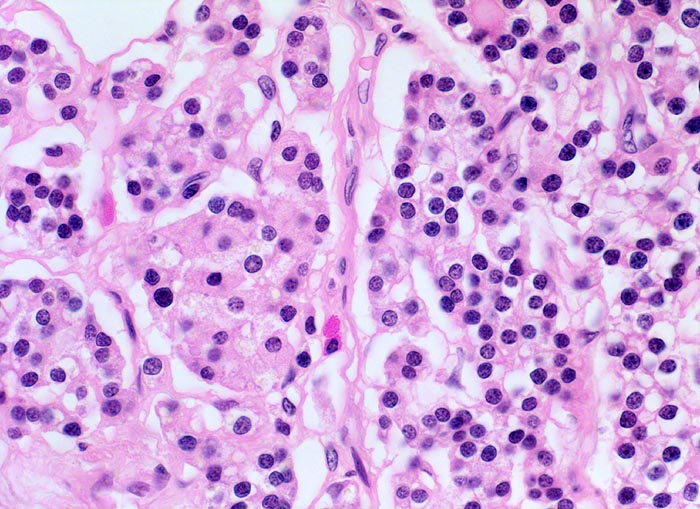

Morphologie der Nebenschilddrüsenhyperplasie:

Morphologisch besteht bei sHPT eine Hauptzellhyperplasie. Makroskopisch findet sich eine meist ungleich ausgebildete Vergrösserung aller Nebenschilddrüsen. Die Grösse der Drüsen entspricht der Schwere und der Dauer des Stimulus. Die im früheren Stadium gefundene diffuse Hyperplasie mit Ersatz des Stromas und der Fettzellen durch chronisch stimulierte Hauptzellen (> 558) (> 559) geht im späteren Stadium in eine noduläre Hyperplasie („Pseudoadenome“) über (> 2358). Die regulierte Anpassung der Nebenschilddrüsen kann in eine Autonomie übergehen (tHPT) (> 3704). Morphologisch besteht in diesem Fall eine unregelmässige noduläre Hyperplasie. Gelegentlich entwickelt sich beim tHPT ein dominanter Knoten, der morphologisch nicht von einem Adenom bei pHPT unterscheidbar ist.

Morphologische Merkmale:

• Knotige vergrösserte Nebenschilddrüse. Abgrenzung der einzelnen Knoten durch breite Fibrosebänder.

• Hyperplasie lipidarmer Hauptzellen.

• Areale mit oxyphilen Zellen.

• Verminderter Fettgehalt (<<35%). Für normale Nebenschilddrüsen gilt: